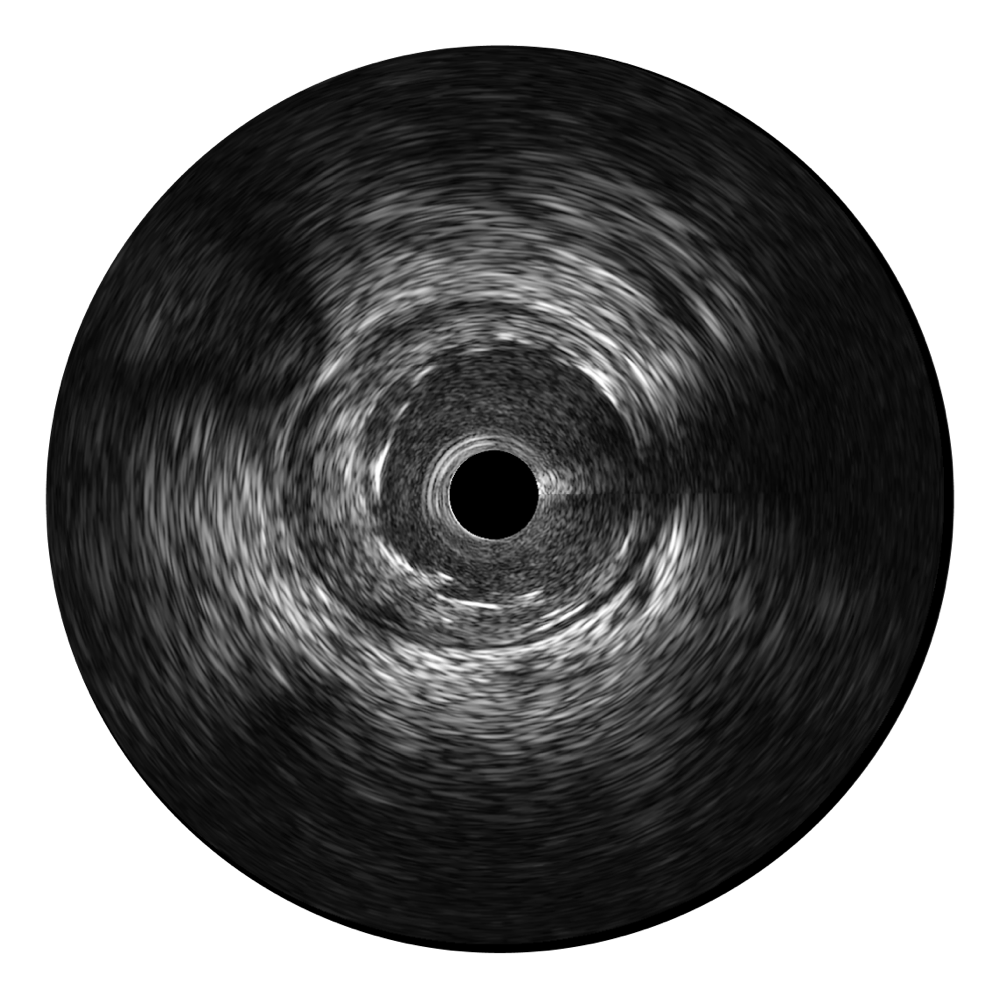

美狮贵宾会官网宽频IVUS图像

对比传统IVUS导管成像,美狮贵宾会官网宽频IVUS图像的近场支架梁显影更细腻,远场中膜外血管仍清晰可辨,兼顾远中近,兼顾分辨力与穿透深度